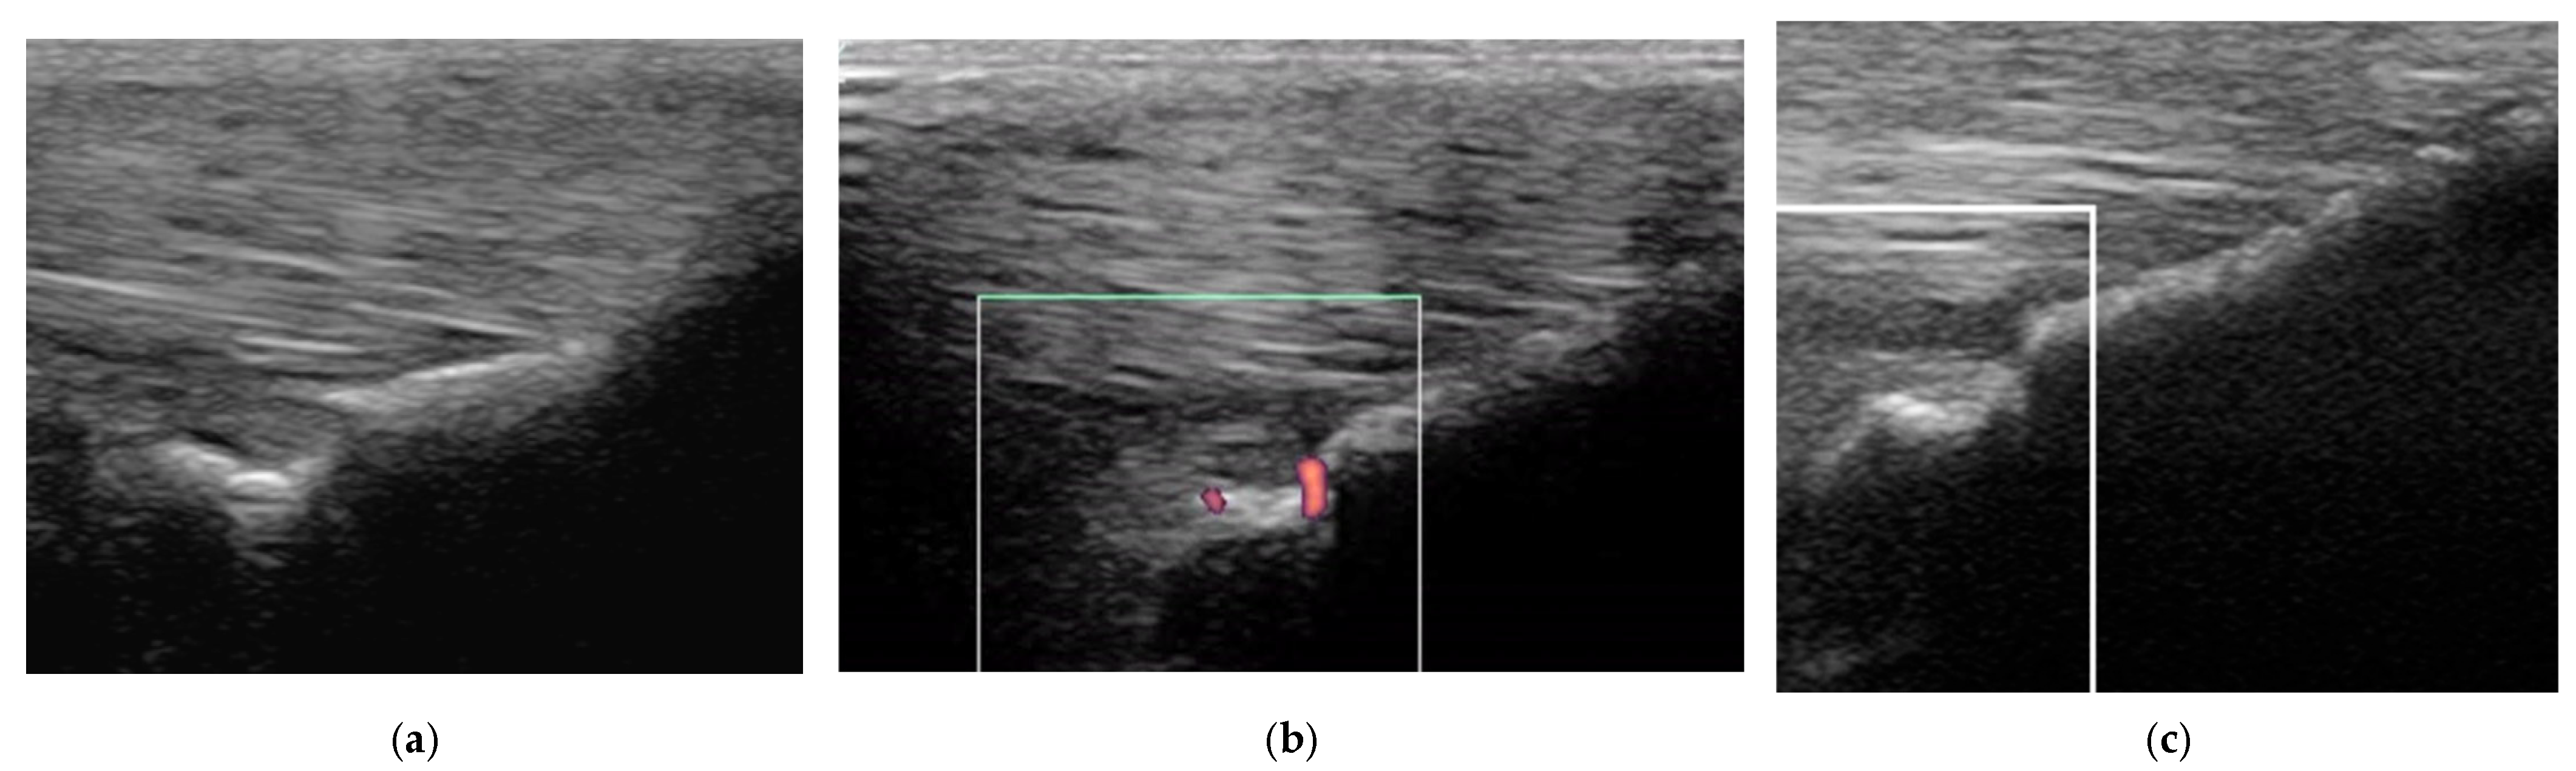

2.3.1. B-Mode Ultrasonography

2.3.2. Power Doppler Examination